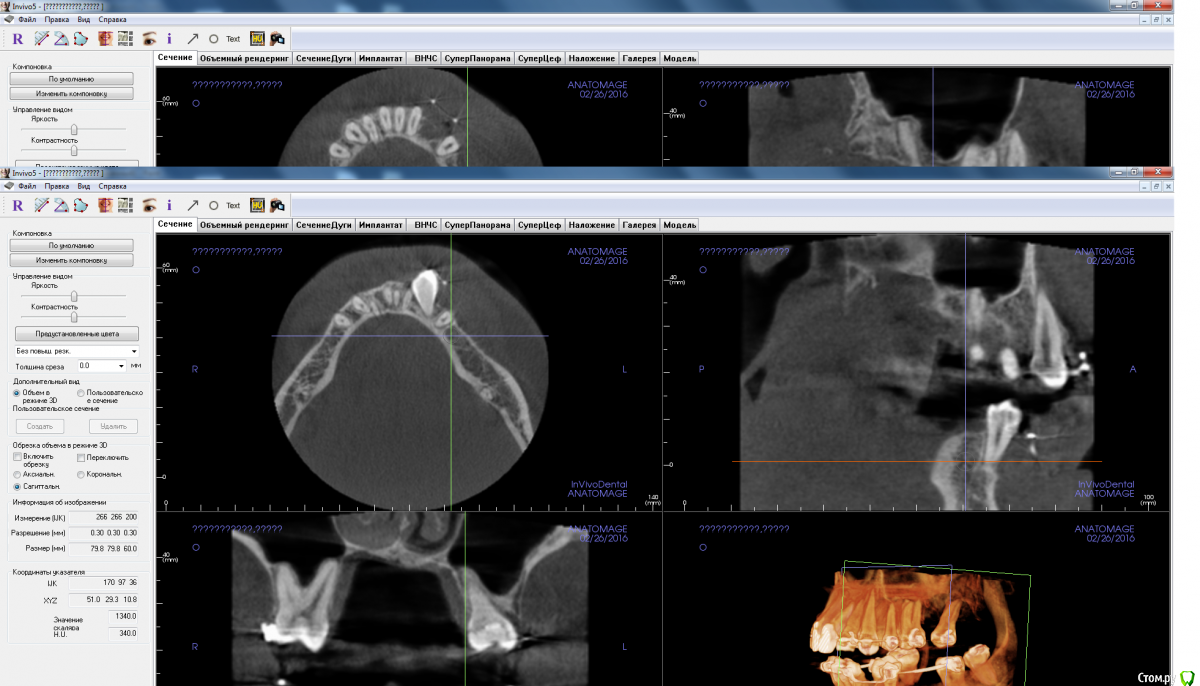

red_butler Опубликовано 8 апреля, 2016 Поделиться Опубликовано 8 апреля, 2016 в распоряжении есть мис и нобельсюда с коническим соединением просятся, и заглубить Ссылка на комментарий

adamskot Опубликовано 9 апреля, 2016 Автор Поделиться Опубликовано 9 апреля, 2016 Пойду на аутоблок, с ретромолярной области, чтобы восполнить потерю вестибулярно в позиции 35.В позиции 36 поставлю одновременнно через 4 мес с 35. Будет более бюджетно, нежели мембрана,ксено и скребок...Надеюсь, срезы сейчас удачны для обзора)) Ссылка на комментарий